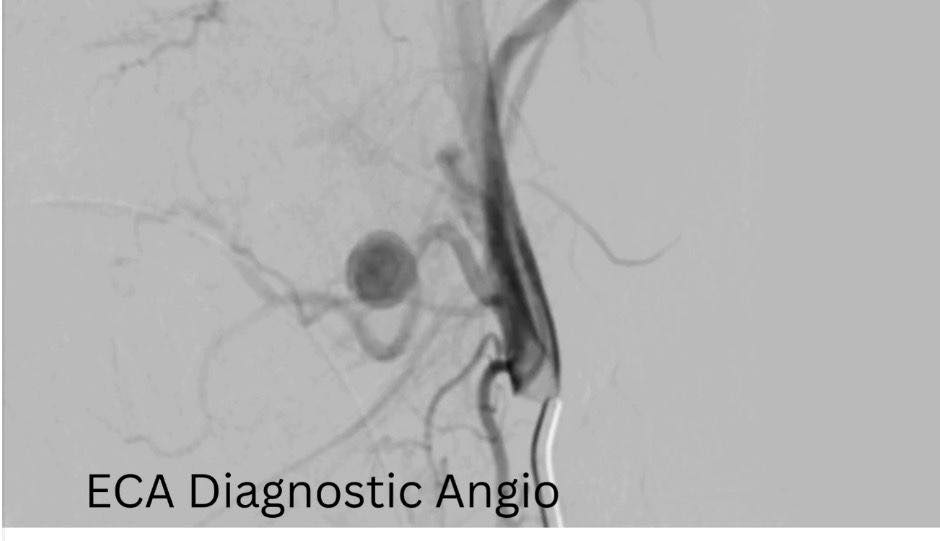

وأكد الدكتور حسان النعماني، رئيس الجامعة، أن سرعة التشخيص ودقة التدخل كانتا عاملين حاسمين في إنقاذ حياة الطفلة، مشيرًا إلى أن جاهزية مستشفيات سوهاج الجامعية والتكامل بين أقسامها المختلفة أسهما في التعامل الفوري مع الحالة وفق أحدث الأساليب العلاجية. وأضاف أن فريق الأشعة التداخلية أجرى الفحوصات والأشعات اللازمة فور وصول الطفلة، والتي كشفت عن وجود تمدد شرياني نازف بأحد الشرايين الرئيسية بالرقبة في جدار الحلق، ما تطلب تدخلاً عاجلاً عالي الدقة.

ومن جانبه، ذكر الدكتور احمد كمال، المدير التنفيذي للمستشفيات الجامعية، أنه تم تجهيز وحدة القسطرة على الفور، حيث نجح الفريق الطبي في غلق التمدد الشرياني باستخدام حلزونات دقيقة عبر القسطرة التداخلية، مما أسهم في السيطرة الكاملة على النزيف دون الحاجة إلى جراحة تقليدية، وتقليل احتمالات المضاعفات.